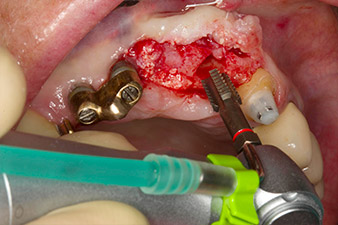

Motorized placement of the implant

Fig. 4: Motorized placement of the implant with the WS-75 L contra-angle handpiece at a ratio of 20:1 (programme P5).

Following primary healing, the soft tissues were shaped using the basally lined bridge. Two months later the site was exposed by a slightly palatal alveolar ridge incision (Fig 2). The dimensions of the alveolar bone proved to be sufficient at position 22. Figures 2 and 4 show the preparation of the implant bed, the tapping and the implantation using Implantmed.